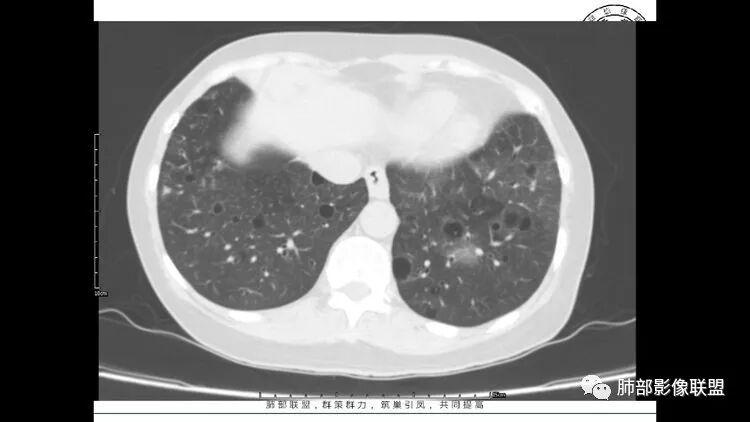

胸CT:1.双肺多发囊性变,以中下肺为主,病变边缘可见肺动脉,部分囊内可见分隔及肺动脉,双下部分肺野周围可见小叶中心结节及树丫征。

2 左肺上叶尖后段 右肺上叶前段 右肺下叶外基底段 结节影,边界清楚,可见柔软毛刺,左肺下叶后基底段混合密度影。

患者中年女性,因右眼红痛1天就诊。胸CT:双肺多发囊性变及结节影,囊以中下肺为多,部分囊内可见分隔及肺动脉,结节部分为实性,部分为混合性,边缘光滑,未见明显毛刺、棘突、胸膜牵拉及血管集束征象。双中下可见支气管扩张及树丫征。淋巴结无明显肿大。综合考虑:一元淋巴细胞间质性肺炎。多元鉴别肺腺癌并转移等恶性病变。

中年女性,双肺多发囊性变,以中下肺为主,病变边缘可见肺动脉,部分囊内可见分隔及肺动脉,左肺上叶较大结节,可见分叶、月牙铲,左肺下叶、右肺中叶磨玻璃病灶,边界清楚,内有空泡,结节,可见尖后段 右肺上叶前段 右肺下叶外基底段 结节影,边界清楚,纵隔淋巴结肿大,

考虑腺癌,淋巴管肌瘤病?LIP?

左肺下叶混杂密度病灶,其内可见空泡,周围ggo清楚,考虑浸润性腺癌。双肺散在多发薄壁囊腔和实性结节,以胸膜下及血管旁分布位于,气囊可见血管贴边征,双肺小叶间隔及中央间质增厚,局部可见磨玻璃影及树芽征,纵隔内淋巴结肿大,考虑LIP

综上,考虑左下肺浸润性腺癌+LIP

双肺多发大小不等囊腔,可见薄壁,部分囊腔内可见血管影,伴双肺多发结节,结合患者眼病及类风湿病史,考虑LIP可能大。另左肺下叶磨玻璃结节,边界清晰,内可见空泡,伴纵膈多发肿大淋巴结,不除外浸润性腺癌可能。

LIP影像重要线索一句话:

双肺下叶分布为主的间质改变(磨玻璃影、小叶间隔增厚)、散在气囊影(常有血管贴边)、边界不清小结节